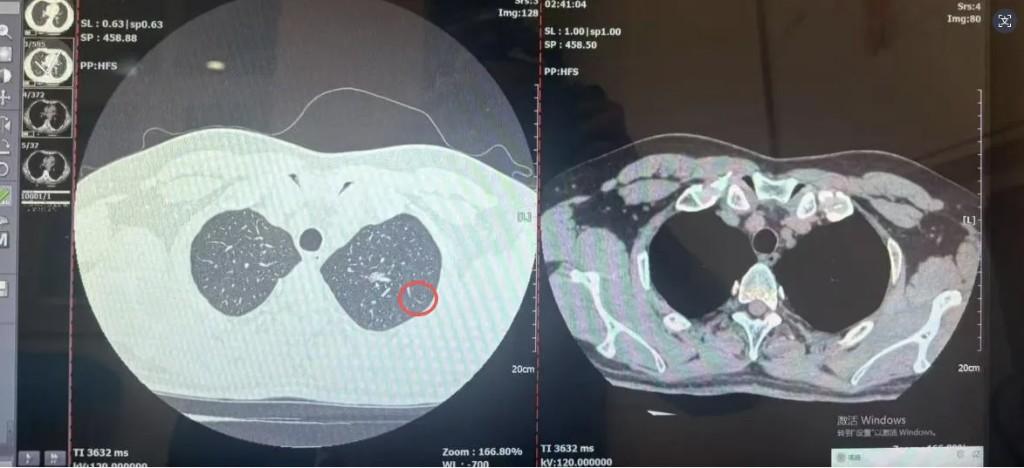

据悉,刘先生平时无三高、慢病等基础疾病,此次因受凉感冒后咳嗽迁延不愈,前往西医一附院排查肺部感染。不料CT报告显示的肺结节影,让他陷入“结节是否为癌”的焦虑,饮食睡眠备受影响。一周后,刘先生参与该院肺结节多学科联合会诊,呼吸与危重症医学科、心胸外科、肿瘤内科、影像科、病理科专家共同研判:结节混合密度、形态具恶性特征,排除感染性病变可能,高度怀疑早期肺癌,且结节位置适合胸腔镜微创手术,创伤小、恢复快。

专家团队的精准分析与明确方案,打消了刘先生的顾虑。他当即决定住院,医护团队迅速完善术前检查、评估手术风险,仅用3天便完成从入院到手术的全流程衔接。心胸外科专家团队顺利实施胸腔镜下左肺上叶部分切除术,术后病理结果确诊为微浸润性腺癌。万幸的是,因发现及时、手术干预迅速,癌细胞未发生扩散,刘先生无需后续放化疗,已达到“临床治愈”标准。